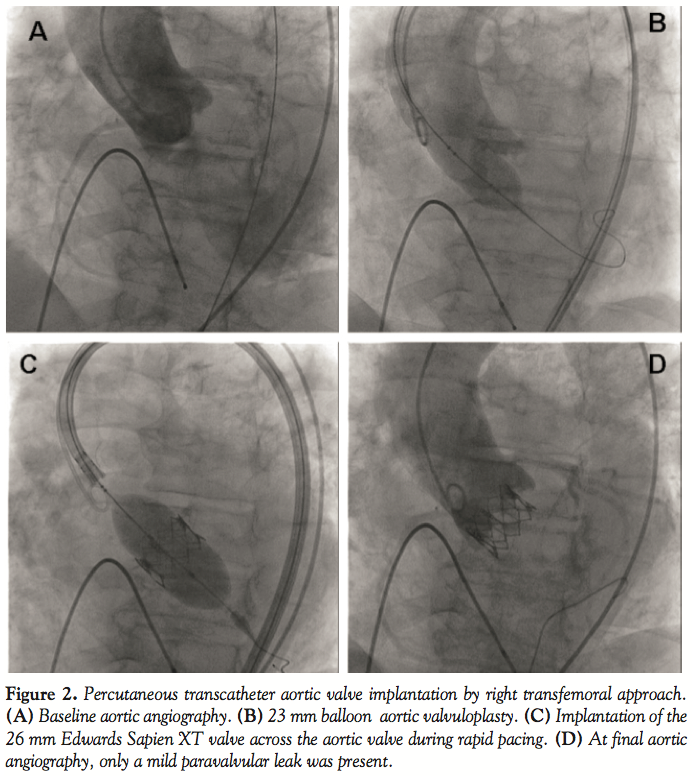

Two weeks later, after a 23 mm balloon aortic valvuloplasty, a 26 mm Edwards Sapien XT transfemoral device (Edwards Lifesciences, Irvine, California) was successfully deployed across the aortic valve (Figure 2). Aortic angiography showed only a mild paravalvular leak. The patient was discharged at day 12 in New York Heart Association class I and dispatched to cardiac rehabilitation.